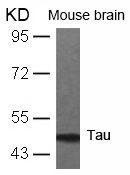

分类: 科研抗体货号: P41321别名: Neurofibrillary tangle protein; Paired helical filament-tau;应用: WB,IHC反应种属: Human,Mouse,Rat